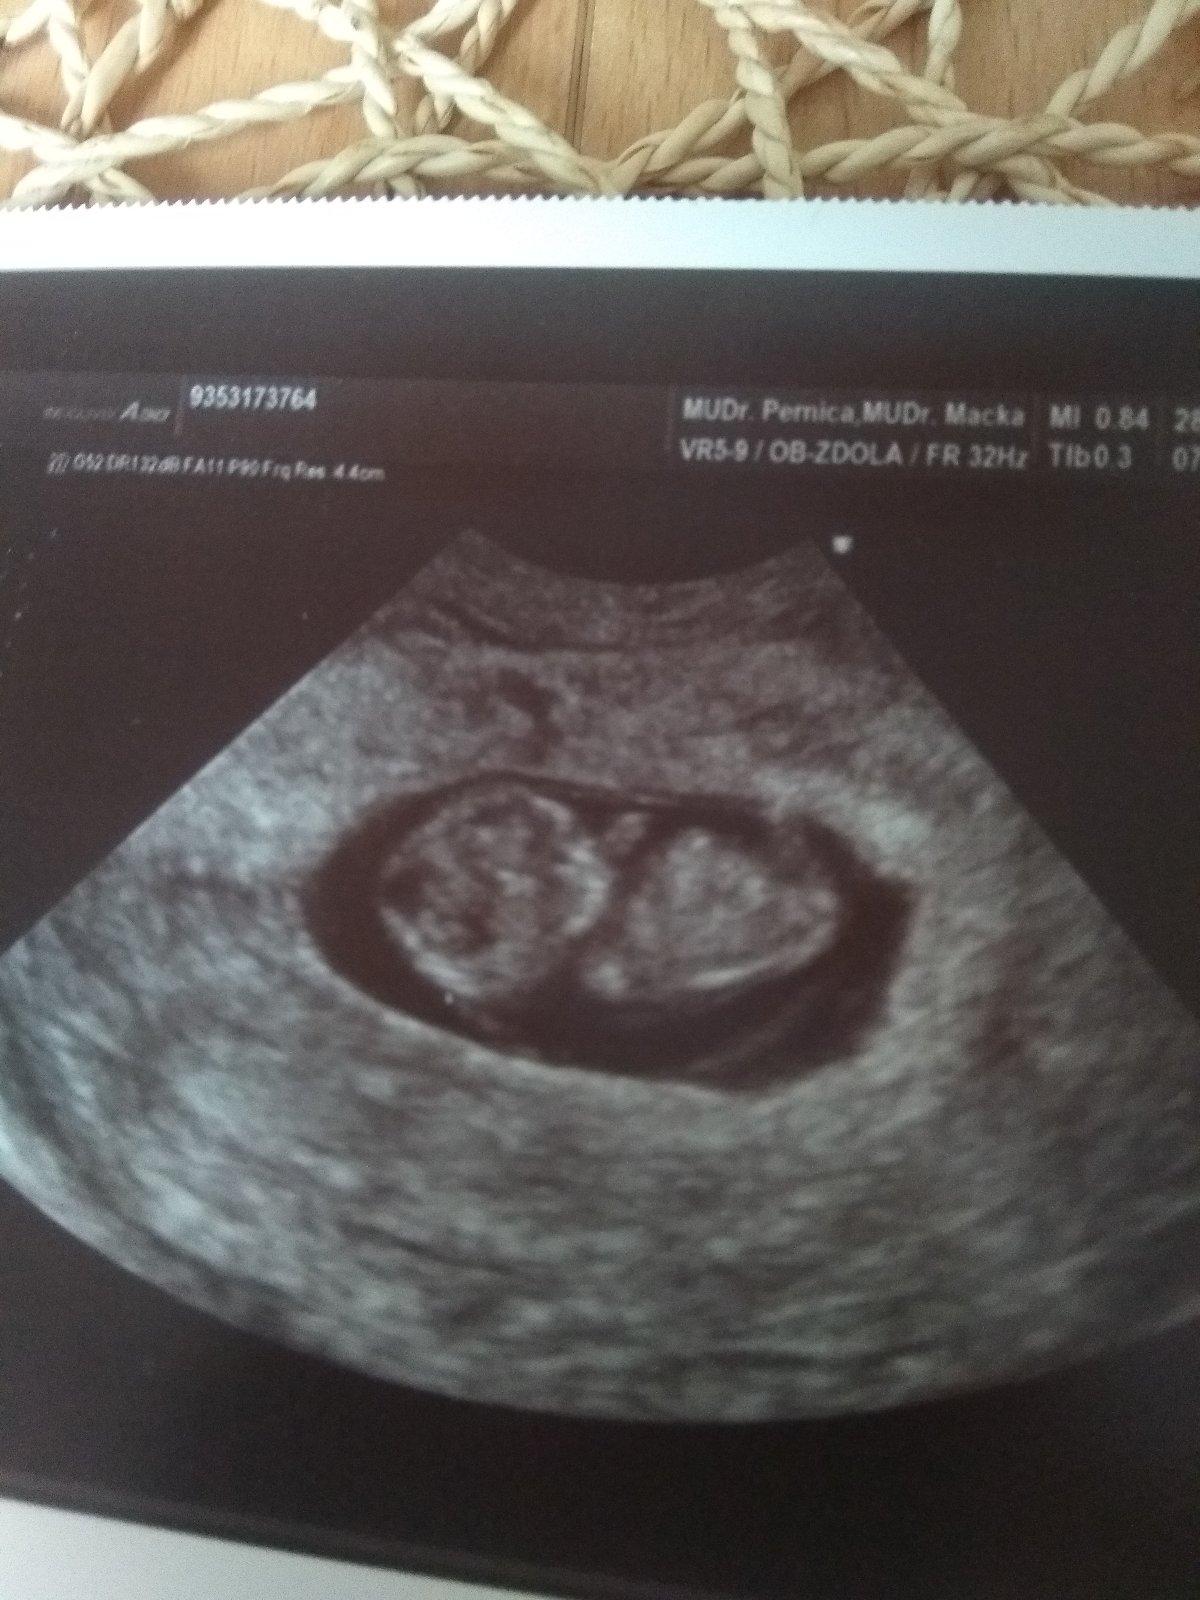

Ahoj přidávám fotečku z patka po přirozeném těhu. Mrňous má 2,5cm. 26.7. jedeme na výsledky ze screeningu.